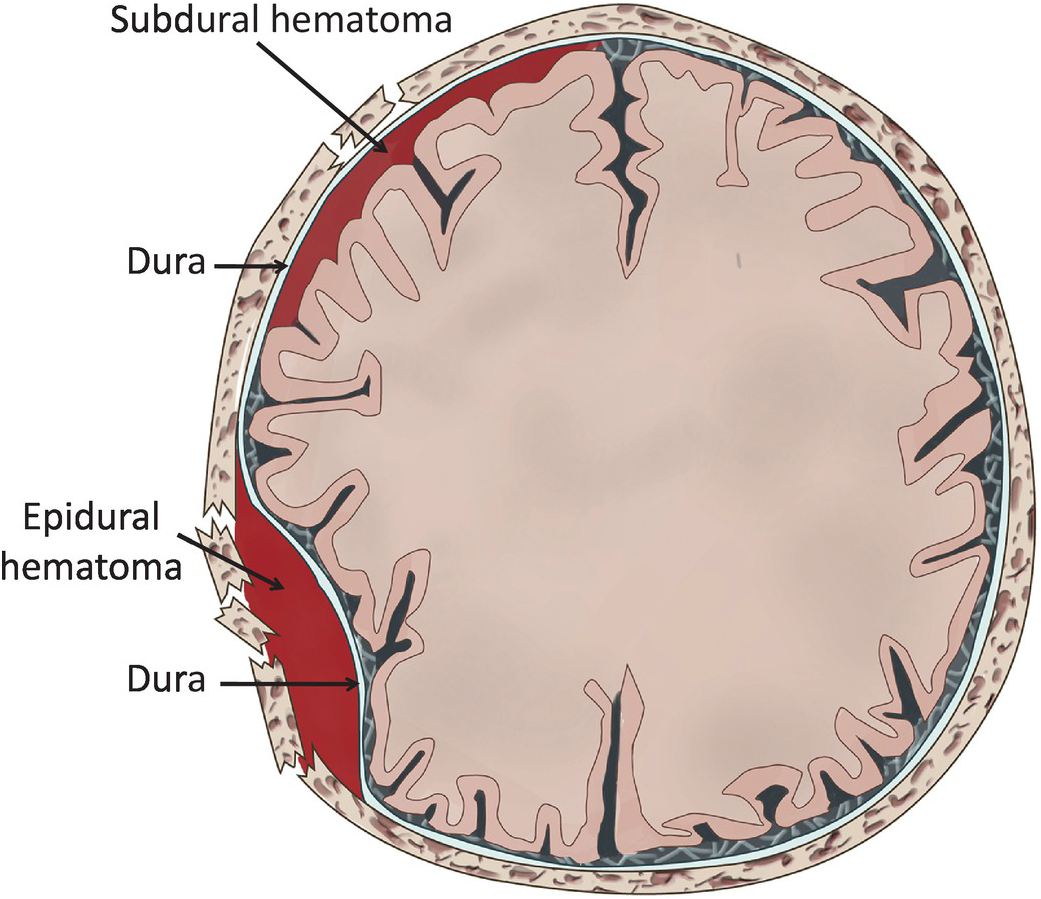

Download Subdural Hematoma Vs Epidural Hematoma Intracranial It’s hard to tell the difference between a subdural hematoma and a stroke. both are serious, but they come from different causes and need different treatments. a subdural hematoma is when blood gathers between the brain and its outer layer. a stroke, or cerebrovascular accident, happens when blood doesn’t reach part of the brain. The only way to differentiate between stroke and chronic subdural hematoma, regardless of symptoms, is with a ct scan of the brain. don’t assume that someone’s symptoms must mean chronic subdural hematoma just because he hit his head recently, either; it can still be a stroke, unrelated to the head trauma. Subdural hematoma: bleeding between the brain and the dura mater, the outermost membrane covering the brain. now, you might be wondering, “are all brain bleeds considered strokes?” the answer is no. while hemorrhagic strokes are a type of brain bleed, not all brain bleeds meet the criteria for a stroke. A subdural hematoma, on the other hand, is a collection of blood between the brain and its outermost covering (the dura mater), often caused by head trauma. both can lead to neurological. There are several types, each with its own set of challenges: 1. intracerebral hemorrhage: bleeding directly into the brain tissue. 2. subarachnoid hemorrhage: bleeding in the space between the brain and the thin tissues that cover it. 3. subdural hematoma: bleeding between the brain and the dura mater, the brain’s tough outer covering. 4. A subdural haematoma is a serious condition where blood collects between the skull and the surface of the brain, causing pressure on the brain and damaging it. it is a form of bleeding inside the head, specifically in the subdural space, which is the area between the dura mater and the arachnoid mater—two of the three layers of tissue.

Hematoma Epidural Vs Hematoma Subdural Vrogue Co Subdural hematoma: bleeding between the brain and the dura mater, the outermost membrane covering the brain. now, you might be wondering, “are all brain bleeds considered strokes?” the answer is no. while hemorrhagic strokes are a type of brain bleed, not all brain bleeds meet the criteria for a stroke. A subdural hematoma, on the other hand, is a collection of blood between the brain and its outermost covering (the dura mater), often caused by head trauma. both can lead to neurological. There are several types, each with its own set of challenges: 1. intracerebral hemorrhage: bleeding directly into the brain tissue. 2. subarachnoid hemorrhage: bleeding in the space between the brain and the thin tissues that cover it. 3. subdural hematoma: bleeding between the brain and the dura mater, the brain’s tough outer covering. 4. A subdural haematoma is a serious condition where blood collects between the skull and the surface of the brain, causing pressure on the brain and damaging it. it is a form of bleeding inside the head, specifically in the subdural space, which is the area between the dura mater and the arachnoid mater—two of the three layers of tissue.

Differences Between Subdural And Epidural Hematoma Epidural Hematoma There are several types, each with its own set of challenges: 1. intracerebral hemorrhage: bleeding directly into the brain tissue. 2. subarachnoid hemorrhage: bleeding in the space between the brain and the thin tissues that cover it. 3. subdural hematoma: bleeding between the brain and the dura mater, the brain’s tough outer covering. 4. A subdural haematoma is a serious condition where blood collects between the skull and the surface of the brain, causing pressure on the brain and damaging it. it is a form of bleeding inside the head, specifically in the subdural space, which is the area between the dura mater and the arachnoid mater—two of the three layers of tissue.